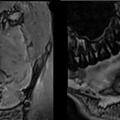

Update zu bildgebenden Verfahren in der Zahnmedizin: Aufnahmen zu Magnetom Free.Max dental edition (ddMRI)